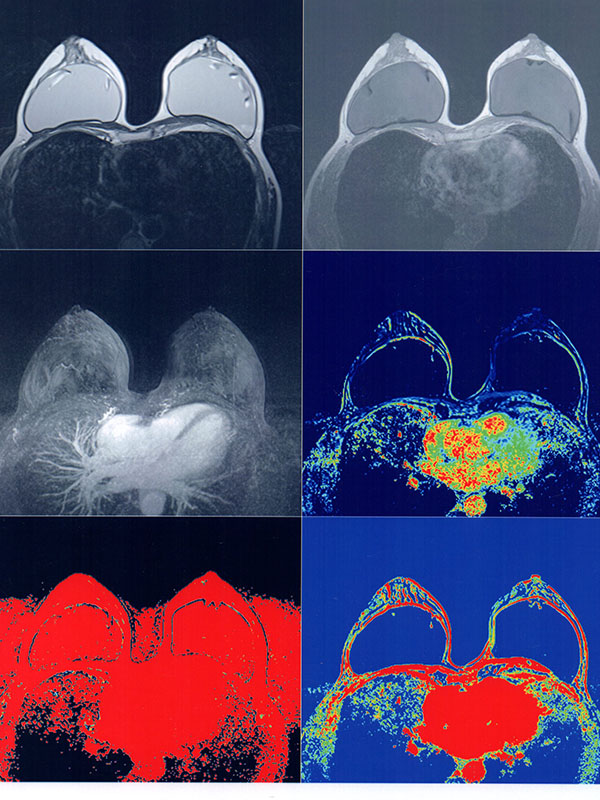

Además se realizan estudios de “Resonancia Fetal” durante el embarazo (a partir de las 12 semanas de gestación), estudios de “Mamas” con análisis anatómico – funcional y estudio de prótesis mamaria.